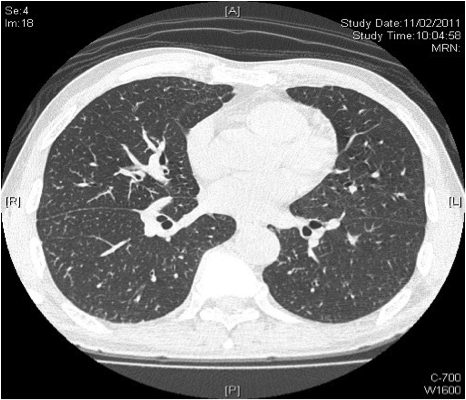

Computer tomography (CT) of chest was done (Fig 2A, 2B). It showed widespread tree-in-bud opacities, septal thickening, mild bronchiectasis and mildly dilated bronchi with wall thickening. The bone window of CT scan showed multiple enlarged mediastinal and hilar lymph nodes. Bronchoscopy with transbronchial biopsy at right lung found bronchiocentric foci of polymorphous inflammatory infiltrate with lymphocytes, plasma cells, eosinophils and neutrophils. There was no granuloma. It suggested interstitial inflammation with eosinophilia.